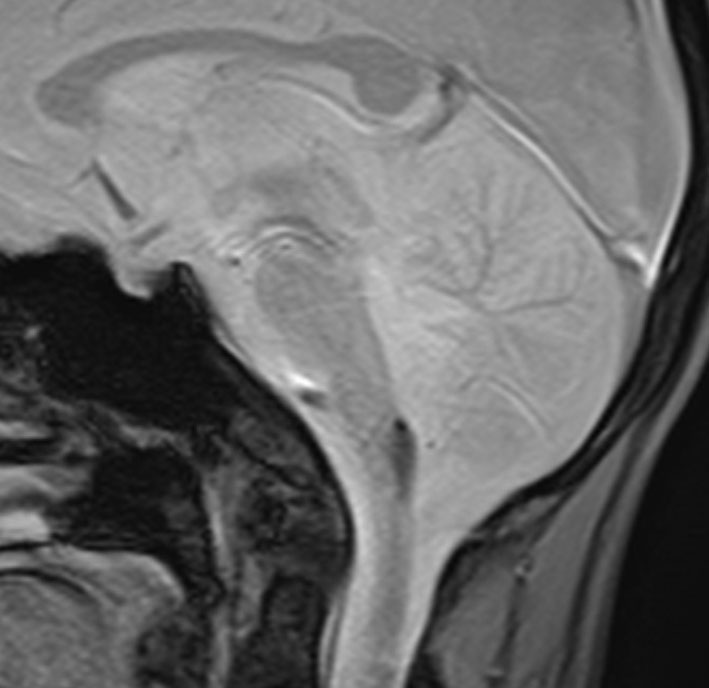

1歳5ヶ月で左小脳半球の髄芽腫になり手術と化学療法して,3歳になってから脳脊髄照射をしました。脳脊髄18グレイ,局所48グレイが入っています。18歳の学生の時のMRIで,左小脳萎縮がありますが普通の生活ができています。

18歳の時に突然,左上下肢の痺れと脱力が生じました。延髄下端から脊髄に小さな出血があります。様子を見ていたら症状はよくなりました。

その後数日の間に,小さな出血を繰り返して,嚥下障害,しゃっくり,頭痛,四肢のしびれなどが出ました。手術をしないで経過を見ました。

7年後のMRIです。延髄脊髄移行部(おそらくC1)に出血痕が残っています。放射線誘発海綿状血管腫といわれるものの画像所見ですが,ほんとのところは静脈閉塞によるうっ血症状と鬱血性の出血といわれています。

症状はすべて良くなりました。今は学校を卒業して,元気に働いています。